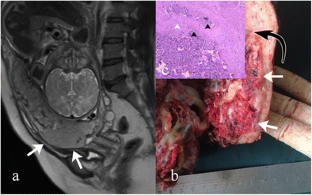

Fig. 1